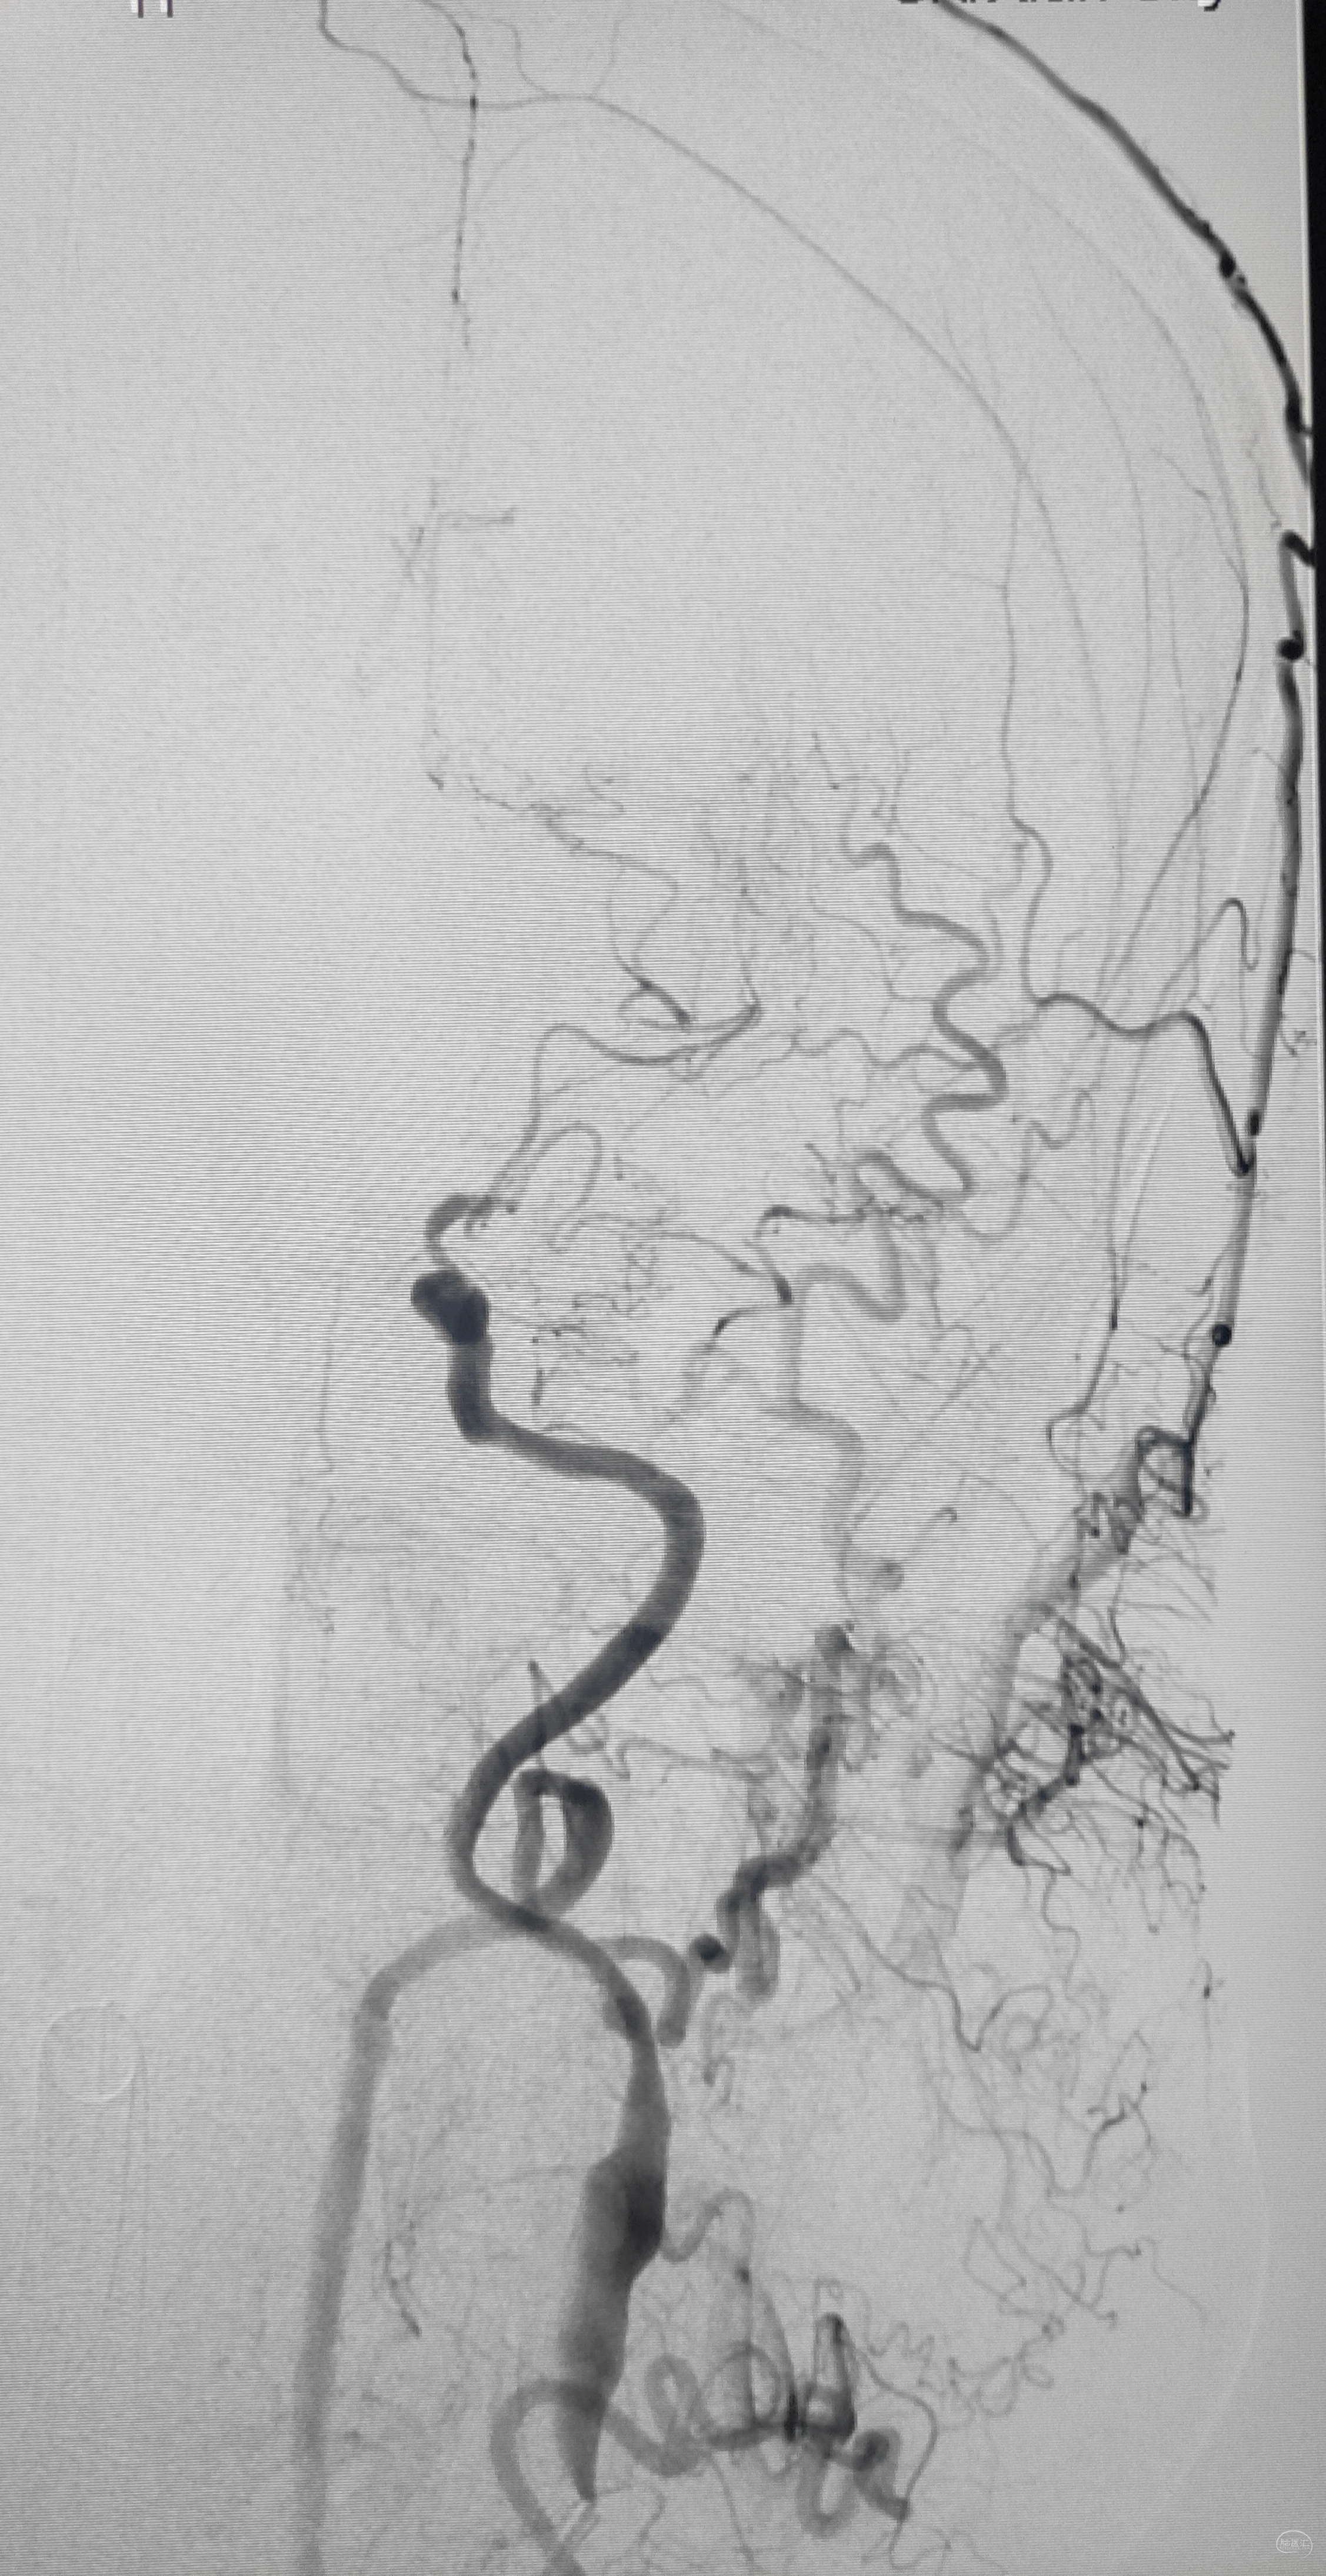

造影显示了依旧闭塞的左侧锁骨下动脉,依旧的逆向盗血

备好心心念的Conquest Pro 8-20,准备开干

双通道

股动脉8F导引导管

桡动脉6F导引导管

望远镜技术

6F导引导管(支撑)+125多功能造影管(支撑+导向)+动脉瘤导管(小支撑)+Conquest导丝(开通利器)

艰苦卓绝的吃线过程,此处心中浮现出一万个草泥马,最终,多角度+超选造影,验证真腔

小球囊+大球囊,梯度预扩

一切看似理想,一切看似简单,诡异的事情还是发生了,8F导引导管死活无法进入左侧锁骨下动脉,各种方法尝试个遍:泥鳅走远,单弯挂口,Sim挂口,屡战屡败(水平退步明显,不应该啊,夹层?),因为怕折腾,因为想安全,怕进假腔,弄出夹层。索性换一个思路:空中接力,构建桡-股动脉大环线

自下向上走不通,那就从上边来

经左侧桡动脉6F导引导管,出加长泥鳅,一路向下,逼近右侧股动脉鞘

以为很难,其实不然,泥鳅头段顺利进入股动脉鞘内,但是问题来了,因为是动脉鞘,有活瓣封口,泥鳅无法逆向穿过动脉鞘入口,何解?

那就利用换鞘技术,桡动脉侧持续给泥鳅张力并顶住(助手),缓慢回撤股动脉鞘至体外(主刀),看到泥鳅后抓紧,后拽;长度足够后,带套管重新置入8F股动脉鞘,完成桡-股动脉大环线建立。

泥鳅两段露头,8F导引导管沿泥鳅攀爬,一把干到左侧肱动脉为止

6F导引导管造影确认支架置入部位

支架导引导管内先通过,再回撤技术,顺利释放雅培9×29球扩支架